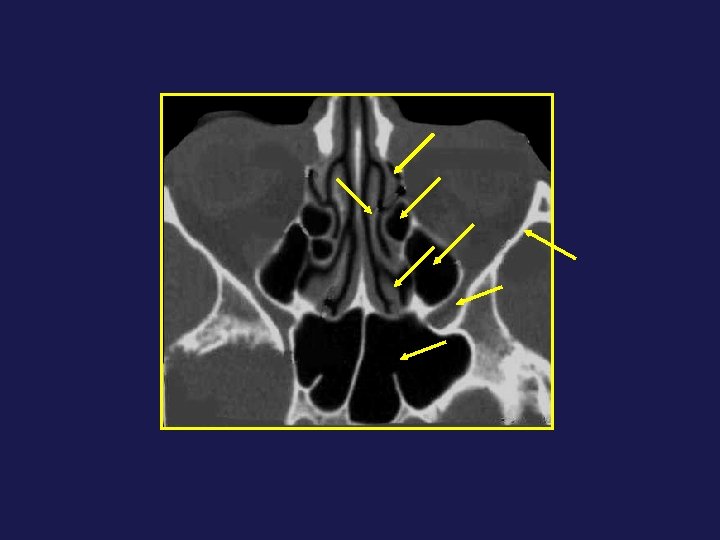

Cellules frontales : obstruction au drainage frontonasal K 1 K 2

K 3 K 4

C supra orbitaire SF Kuhn 3 SF Kuhn 1